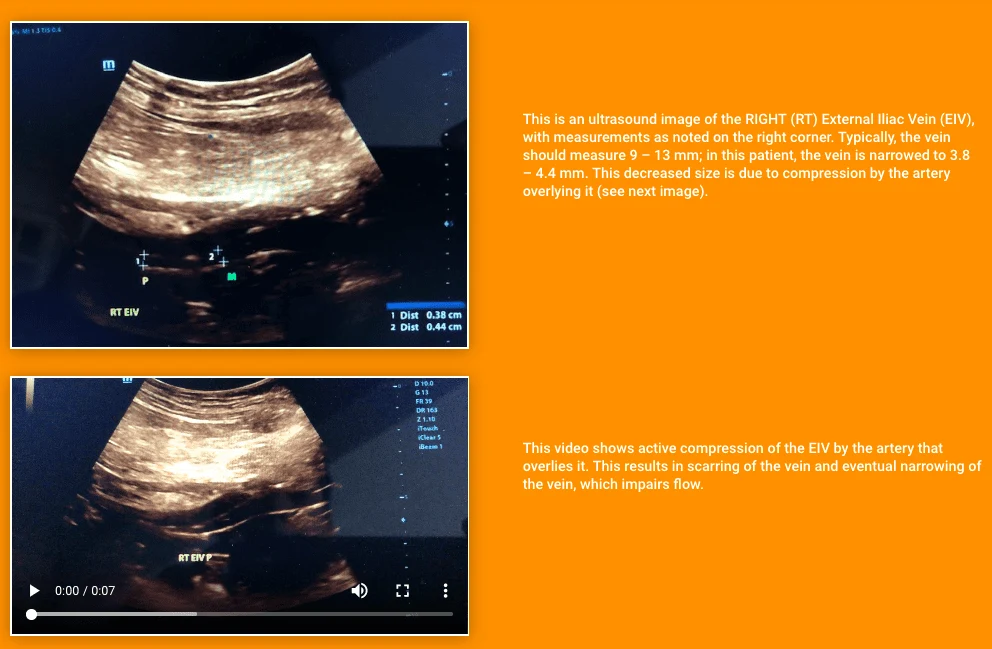

Ultrasound Image

May-Thurner Syndrome